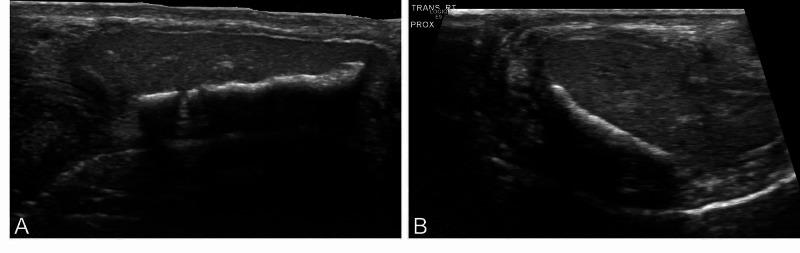

Human penile ossification is a rare urologic condition with approximately 40 cases reported in the literature so far. While bone is essential for penetrative intercourse in many non-human mammals, human penile ossification appears to be part of a metaplastic process occurring after injury or trauma. Conditions such as Peyronie's disease, diabetes mellitus, local trauma, and end-stage renal disease have been associated with this entity. We report the case of a 65-year-old male with penile curvature and a history of painful intercourse who underwent partial excision and grafting with bovine pericardial graft and was found on pathologic examination to have penile ossification.

人类阴茎骨化是一种罕见的泌尿系统疾病,迄今为止文献报道约有40例。虽然在许多非人类哺乳动物中,骨骼对于性交至关重要,但人类阴茎骨化似乎是损伤或创伤后发生的化生过程的一部分。佩罗尼氏病、糖尿病、局部创伤和终末期肾病等情况已与该病症相关联。我们报告了一例65岁男性病例,该患者有阴茎弯曲和性交疼痛史,接受了部分切除并用牛心包移植物进行移植,病理检查发现有阴茎骨化。